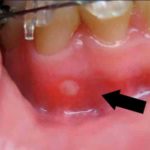

Белые ранки на десне являются признаком афтозного стоматита, который чаще всего диагностируют у девушек. В ротовой полости происходит образование большого количества язвочек, у которых отсутствуют четкие границы. Иногда они проходят в течение 5-7 дней без лечения, но потом появляются снова, потому что не устранена основная причина их образования. Помимо этого, белые ранки на десне – явный признак язвенного гингивита, который развивается на фоне кариеса, низкого иммунитета, курения.

Родителям стоит насторожиться, если у ребенка ранки появились на деснах около зубов, долго не проходят, приводят к дискомфорту. Обычно малыш отказывается от еды, чувствует вялость, усталость, с трудом говорит. При воспалительных процессах поднимается температура, которую сложно сбить обычными препаратами, отсутствует аппетит. В интернете часто публикуют, как выглядит рана на десне – фото иллюстрирует образования у детей и взрослых. Причем у малышей обычно появляется сразу 2 воспаления и более.

Первое, что всегда рекомендуют сделать стоматологи – убрать зубной камень. Именно под ним могут находиться инфекционные очаги, провоцирующие язвочки и другие проблемы. Если человек посещает врача нерегулярно, отложения на зубах твердеют, сдавливают мягкие ткани, вызывая повышенную чувствительность к любым раздражениям. И часто, когда ранки появляются на десне, фото показывает, что рядом присутствует зубной налет. После его снятия врач осматривает ротовую полость, а также выслушивает жалобы пациента. Обязательно выясняют наличие хронических заболеваний.